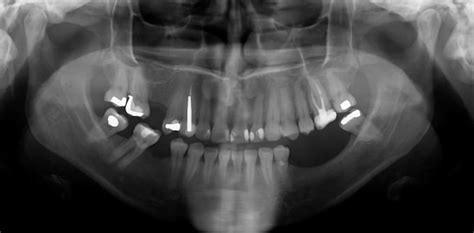

La pérdida de hueso dental es un problema que afecta a muchas personas y puede comprometer la salud bucal si no se trata a tiempo. Se trata de una afección en la que el tejido óseo que sostiene los dientes disminuye progresivamente, provocando movilidad dental y, en casos avanzados, la pérdida de piezas dentales.

La pérdida de hueso dental se refiere al deterioro o disminución de la masa ósea que rodea y sostiene los dientes. Este hueso alveolar es esencial para mantener los dientes firmes en su lugar y proporcionar un soporte adecuado para masticar y hablar. Cuando se pierde masa ósea en esta zona, los dientes pueden comenzar a moverse, lo que lleva a problemas de estabilidad y funcionalidad en la boca.

El hueso alveolar, ubicado en el maxilar superior e inferior, contiene las cavidades donde se alojan las raíces de los dientes. Cada diente está fijado a un hueco denominado alvéolo. Dentro del hueso hay perforaciones que contienen los vasos sanguíneos. El hueso alveolar es dinámico y puede cambiar en respuesta a estímulos, como la presión ortodóntica o la pérdida de un diente.

- Enfermedad Periodontal (Periodontitis): La periodontitis, o piorrea, es una causa principal de la pérdida de hueso dental. Esta infección bacteriana afecta las encías y el hueso que sostiene los dientes. Cuando alguien presenta esta enfermedad periodontal, padecen de inflamación crónica de las encías y la degradación del tejido de soporte de los dientes, incluyendo el hueso alveolar. Las bacterias en la placa dental son las responsables de esta infección que progresa hacia el hueso.

- Pérdida o extracción de dientes: La causa más habitual de disminución de la densidad ósea es la pérdida de dientes que no se reemplazan. Cuando se pierde un diente y no se reemplaza a tiempo, el hueso que lo sostenía deja de recibir estímulos y comienza a reabsorberse. La falta de estímulo de masticación en esa área causa la pérdida gradual de hueso.